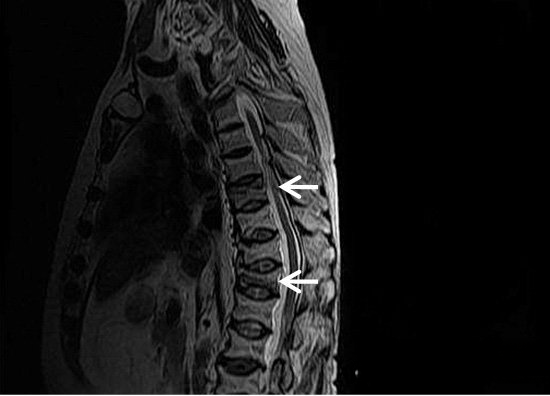

7a1720be8baf1259e6575c4ff03a3773.png

图-13  75岁男性因使用糖皮质激素导致的骨质疏松。(A)矢状位T2显示椎体压缩,信号减低和增高混合。(B)SE-DWI显示一个高信号区(箭头),这是由肺部转移引起的。